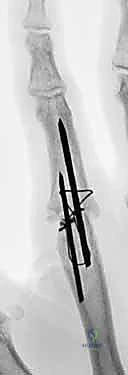

- Kirschner Wire (K-wire) Fixation:

- Advantages: Simplicity of technique, ready availability, low-cost implants. Historically, fusion rates up to 99% have been reported.

- Disadvantages: Less rigid fixation, often requiring additional external immobilization (splint/cast) which can lead to stiffness in surrounding joints. Higher risk of infection (superficial pin site, deep wound, osteomyelitis). Potential for pin migration. Minimal compression across the fusion site, which is biomechanically less favorable.

- Tension Band Fixation: This is a biomechanically superior method, often considered the gold standard for small joint arthrodesis.

- Mechanism: It combines parallel Kirschner wires for rotational control with interosseous wiring for compression. The genius of this